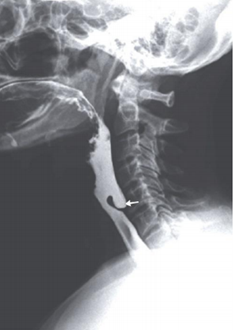

Paciente de 58 anos com queixa de dor cervical, engasgos ao se alimentar e regurgitação de alimentos não digeridos. Realizou exame de radiografia contrastada ao lado:

enunciado 1517396-1

Em relação ao caso, assinale a alternativa correta.